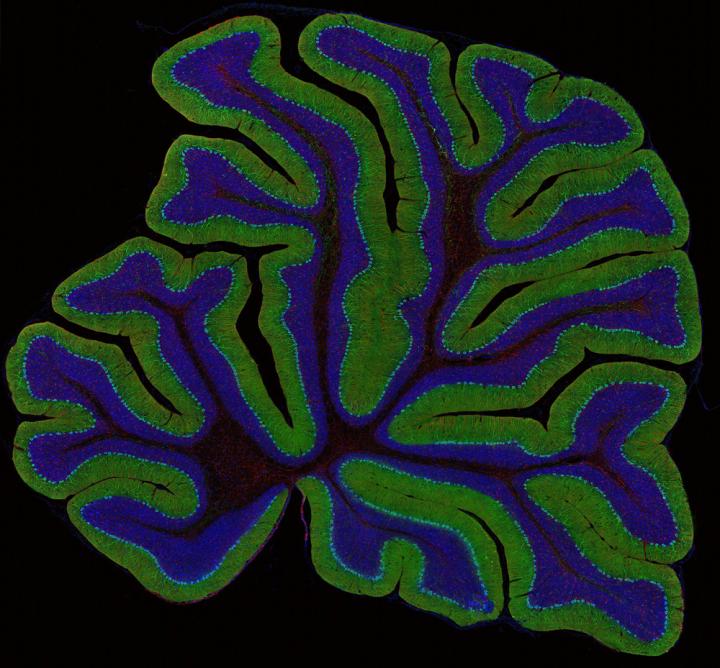

Cal-BRAIN, a California research grants program that aims to revolutionize our understanding of the brain, has selected 16 projects to receive inaugural seed grants of $120,000 each. The projects represent efforts around the state to create new technologies capable of measuring brain activity in greater depth, breadth and detail than is currently possible.

An initiative led jointly by UC San Diego and the Lawrence Berkeley National Laboratory, Cal-BRAIN is short for California Blueprint for Research to Advance Innovations in Neuroscience. The program was signed into law in June 2014 and is the California complement to the federal BRAIN Initiative announced by President Barack Obama in 2013.

The projects will seek to measure four different aspects of the brain's activity: electrical activity, neurochemical activity, metabolic activity and gene activity. The technological strategies include advances in microscopy, brain imaging, sensors based on nanotechnology, and neural prosthetics, explained UC San Diego's Ralph Greenspan, who co-directs Cal-BRAIN with Paul Alivisatos of the Lawrence Berkeley National Laboratory.

All of the projects aim at innovations that will be applicable to the full spectrum of brain disorders, Greenspan said, and several are specifically keyed to traumatic brain injury, paralysis, epilepsy and Alzheimer's.